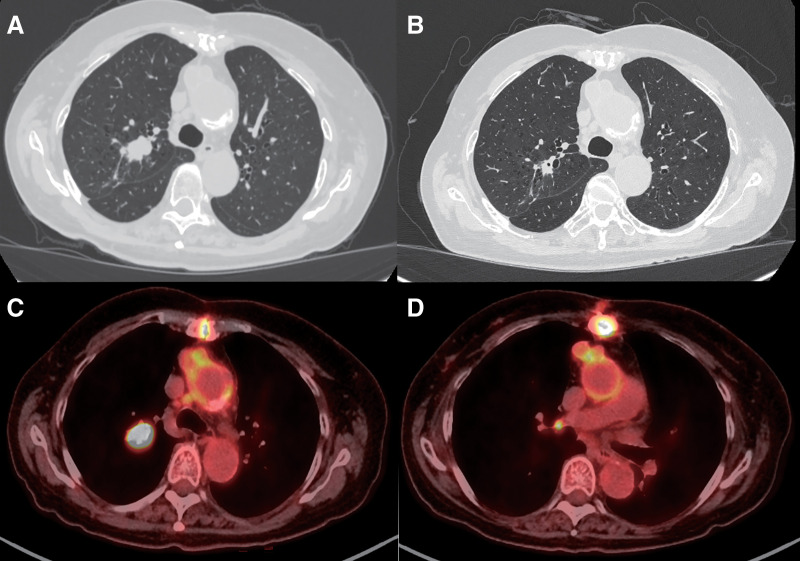

Case presentation: A 74-year-old woman was diagnosed with slow-growing squamous cell carcinoma of the right upper lobe during treatment for another disease. Imaging studies revealed a small nodule suggestive of pulmonary metastasis in the right upper lobe and hilar lymph node metastasis. The patient was initially diagnosed with primary lung cancer of the right upper lobe (cT3N1M0, Stage IIIA, TNM Classification, 8th edition), and neoadjuvant nivolumab combined with chemotherapy was planned every 3 weeks for three cycles. After the first cycle, the patient experienced drug-induced kidney injury. Nivolumab and chemotherapy were discontinued, and surgical resection was planned. However, a laboratory analysis on the day before surgery revealed elevated free triiodothyronine and free thyroxine, and decreased thyroid-stimulating hormone. Subsequent examination led to a diagnosis of destructive thyroiditis due to irAEs, and surgery was postponed. Dexamethasone was administered orally for 1 week, and once the thyroid function showed consistent improvement, a thoracoscopic right upper lobectomy was performed. The patient progressed without any other complications after surgery.